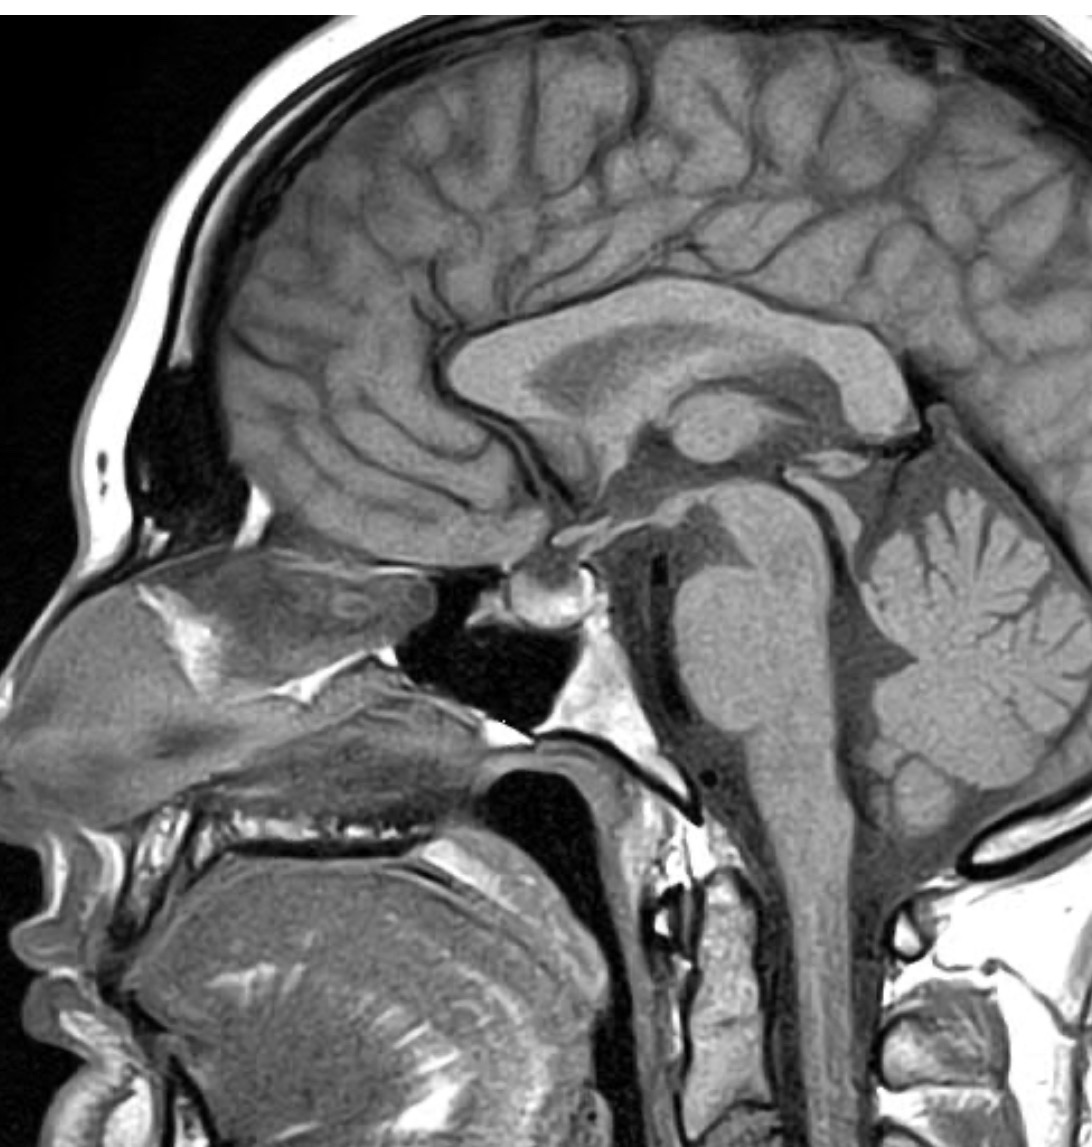

My name is Hannah Carrico, and in November 2024, my life changed when I was diagnosed with a benign brain tumor called a prolactinoma.

While I am incredibly grateful that it isn’t cancer, this diagnosis has still completely altered my life. My tumor has previously hemorrhaged in my brain, making it unstable and requiring urgent surgical intervention. Because of the complexity, I’ve already been passed between multiple neurosurgeons, and I am now scheduled for surgery at the Mayo Clinic in February.

This tumor doesn’t just exist on an MRI—it affects my hormones, vision, immune system, mental health, and fertility. It has impacted every part of my life.

I will be posting my MRI images below, not only to show the tumor but also to raise awareness for prolactinomas and invisible illnesses like mine.